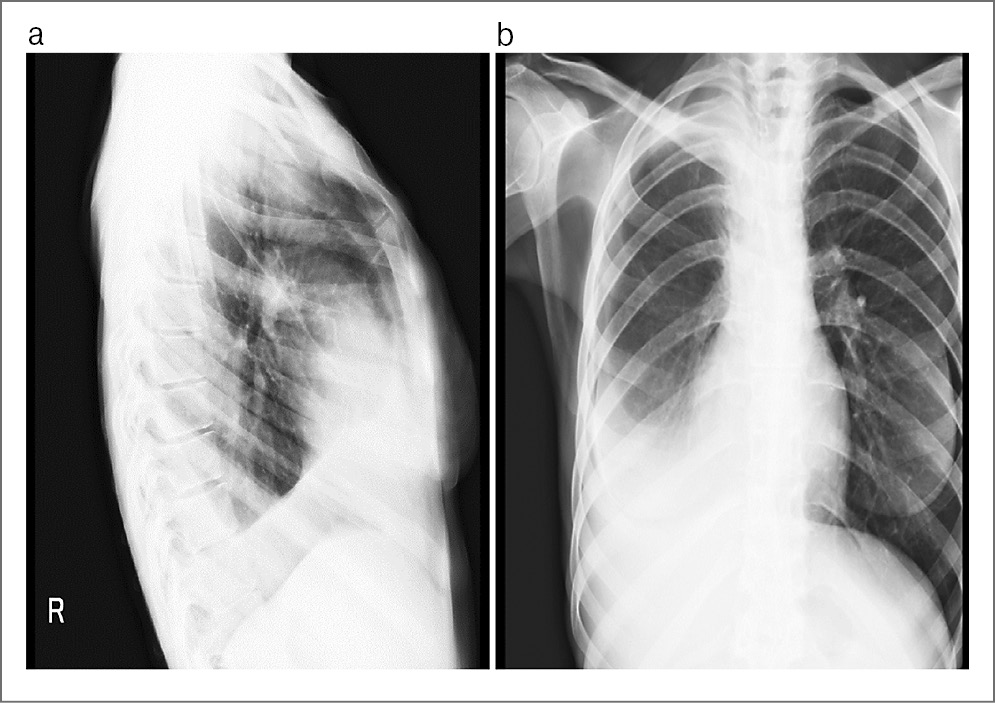

Выполнена повторная рентгенография органов грудной клетки, при которой выявлены рентгенологические признаки правостороннего гидроторакса, ателектаза верхней доли правого легкого (рис. 2, а, b).

Рис. 2 (а, b). Рентгенологические признаки правостороннего гидроторакса, ателектаза верхней доли правого легкого.